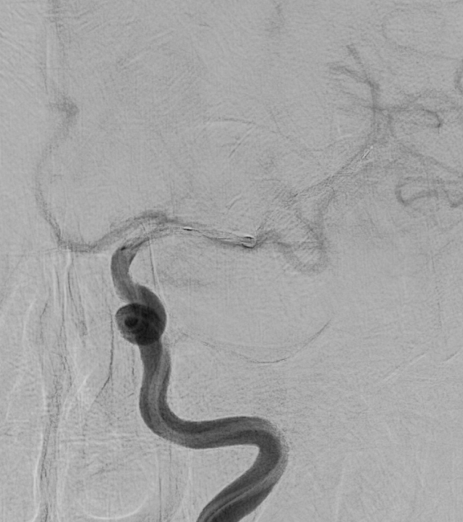

Apoplexy 14

【脳動脈瘤;矢印の部位】

治療の方法は、開頭して動脈瘤にクリップをかけるクリッピングという方法と、コイル塞栓術といって頭を開けないでカテーテルで治療する方法があります。どちらの手段にも有利な点と不利な点があり、当院では動脈瘤の場所、形状、患者さんの状態などに応じて両者を使い分けています。